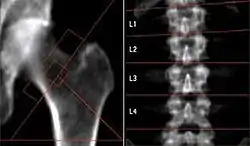

In these images are a Dual Energy X-ray Absorptiometry (DEXA) scans of a human hip bone, left, and a human spine, right. Credit: Thomas Lang, University of California in San Francisco, NASA.

The image on the right shows the loss of bone mass apparently due to long-term microgravity on the International Space Station. "[A]stronauts, on average, lost roughly 11 percent of their total hip bone mass over the course of their mission."[4]